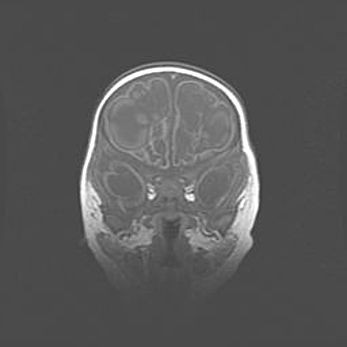

Наружная гидроцефалия с возможной атрофией височных областей.

Возраст: 28 дней

Вес: 3670 г

Пол: мужской

Окружность головы: 38 см

Срок гестации: 40 недель

Гидроцефалия головного мозга у новорожденных – это заболевание, которое характеризуется скоплением избыточного количества спинномозговой жидкости в желудочковой системе головного мозга в результате затруднения её перемещения от места выработки к месту поглощения в кровеносную систему или вследствие нарушения абсорбции. При открытой наружной форме гидроцефалии у новорожденных расширяются и переполняются субарахноидные пространства.

При нормотензивных  формах,  которые,  как  правило,  являются  следствием  перенесенных ишемических  повреждений  паренхимы  мозга,  возможно  сочетание микроцефалии  с нормотензивной гидроцефалией. В основе данных изменений лежит атрофия больших полушарий с преимущественной  локализацией  в  лобно-височных  областях.